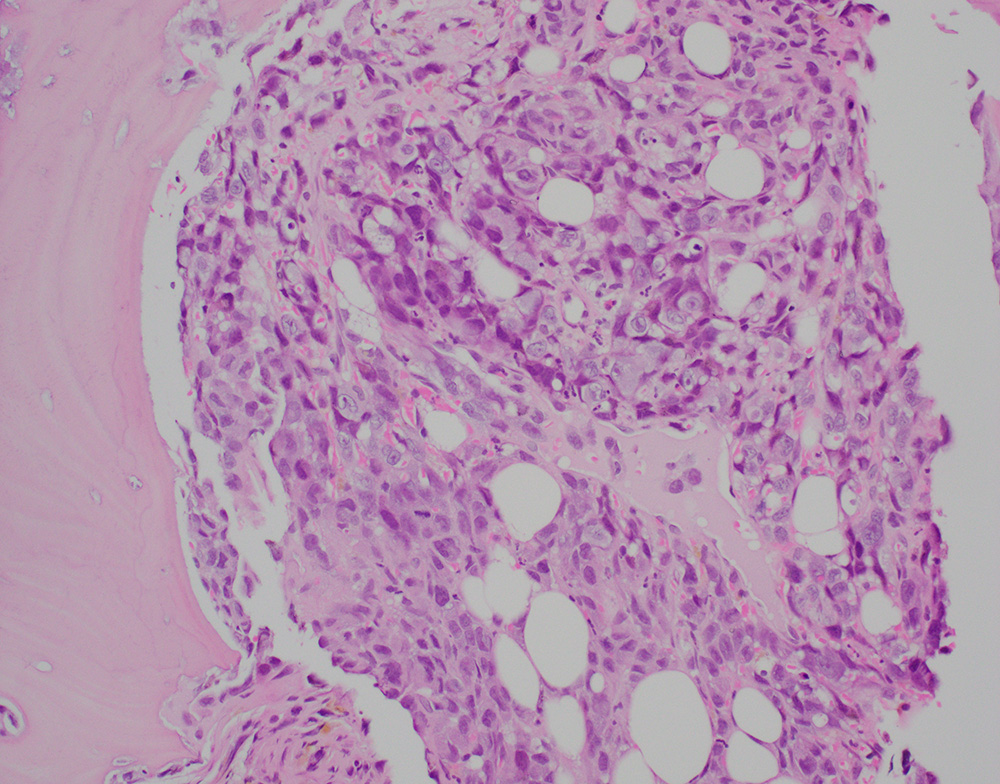

A bone biopsy showed a poorly differentiated epithelioid neoplasm with pleomorphic nuclei, prominent nucleoli (Figures-1, 2) with foci of necrosis. The tumor cells were positive for keratin 7 (Figure-3) with patchy positivity for pan-keratin, while they were negative for PAX8, SOX10, keratin 20, TTF-1, p40, NKX3.1, CDX2, and GATA3. Given the keratin positivity, the tumor was felt to represent metastatic carcinoma. The patient also had several skin nodules involving the posterior leg. A skin biopsy demonstrated numerous irregularly shaped anastomosing and infiltrative vascular channels lined by atypical endothelial cells (Figure-4). The neoplastic cells were positive for ERG, CD31 and CD34 (Figure 5). Re-evaluating and staining the bone biopsy with vascular markers showed positive ERG staining in the neoplastic cells.